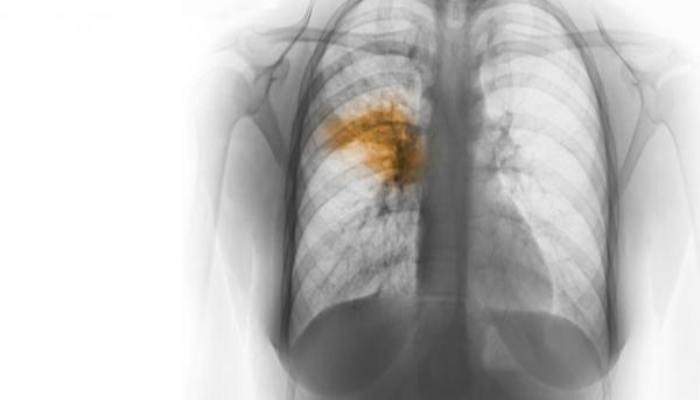

जानलेवा हो सकता है निमोनिया, ये लक्षण है तो तुरंत कराएं इलाज

नई दिल्ली। आज वर्ल्ड निमोनिया डे मनाया जा रहा है। निमोनिया एक ऐसी बीमारी है जो आसानी से लोगों की जान ले सकती है। इसलिए इस बीमारी के प्रति आपको जागरूक होने की आवश्यकता है। [caption id="attachment_448791" align="aligncenter" width="700"]World Pneumonia Day जानलेवा हो सकता है निमोनिया, ये लक्षण है तो तुरंत कराएं इलाज[/caption] निमोनिया ज्यादातर बच्चों और बुजुर्गों को अपना शिकार बनाता है क्योंकि इनका इम्यून सिस्टम कमजोर होता है। निमोनिया होने पर फेफड़े संक्रमित हो जाते हैं और कफ, बुखार और ठंड लगने जैसी समस्याएं हो सकती हैं। यह भी पढ़ें- पानीपत में कांग्रेस की ट्रैक्टर रैली, सेलजा बोलीं- बरोदा की जनता ने भाजपा के चेहरे को किया बेनकाब [caption id="attachment_448793" align="aligncenter" width="700"]World Pneumonia Day Hospital nurse helps a senior woman breath through an oxygen mask.[/caption] अगर निमोनिया का वक्त रहते इलाज नहीं करवाया जाता तो ये जानलेवा साबित हो सकता है। इसलिए अगर आपको कफ, बुखार, सांस लेने में तकलीफ या थकान जैसे अन्य लक्षण है तो सावधान हो जाएं और तुरंत डॉक्टर के पास जाकर उपचार करवाएं। यह भी पढ़ें- अमेरिका में कोरोना की दूसरी ‘लहर’ का कहर, एक दिन में 2 लाख से ज्यादा मामले [caption id="attachment_448794" align="aligncenter" width="700"]World Pneumonia Day जानलेवा हो सकता है निमोनिया, ये लक्षण है तो तुरंत कराएं इलाज[/caption] शुरूआती स्टेज में निमोनिया का पता चलने पर इसका इलाज संभव है। निमोनिया के रोगियों को एंटी-बायोटिक दवाएं दी जाती हैं। बता दें कि पांच साल से कम आयु वर्ग के बच्चों की मृत्यु का प्रमुख कारण निमोनिया है। जानकारी के मुताबिक भारत में सालाना 5 वर्ष से कम उम्र के बच्चों में साढ़े चार लाख निमोनिया के शिकार होते हैं।